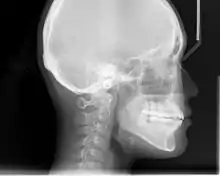

Cephalometric analysis depends on cephalometric radiography to study relationships between bony and soft tissue landmarks and can be used to diagnose facial growth abnormalities prior to treatment, in the middle of treatment to evaluate progress, or at the conclusion of treatment to ascertain that the goals of treatment have been met.[5] A Cephalometric radiograph is a radiograph of the head taken in a Cephalometer (Cephalostat) that is a head-holding device introduced in 1931 by Holly Broadbent Sr. in USA.[6] The Cephalometer is used to obtain standardized and comparable craniofacial images on radiographic films.

Lateral cephalometric radiograph is a radiograph of the head taken with the x-ray beam perpendicular to the patient's sagittal plane. Natural head position is a standardized orientation of the head that is reproducible for each individual and is used as a means of standardization during analysis of dentofacial morphology both for photos and radiographs. The concept of natural head position was introduced by Coenraad Moorrees and M. R Kean in 1958[9][10] and now is a common method of head orientation for cephalometric radiography.[11][12]